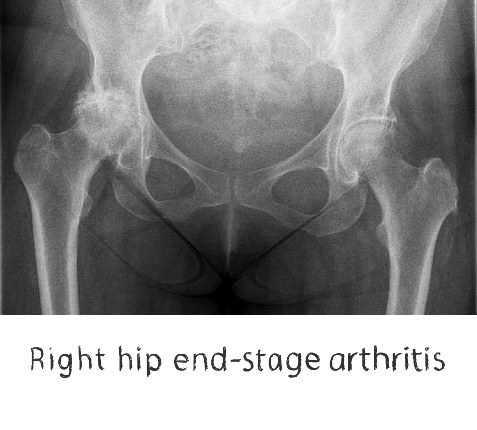

Plain film x-rays are taken to assess the joint

These are usually taken prior to your appointment. These help to confirm the diagnosis, assess the wear pattern and look for particular deformities. They can show old metalware and its position in the bone.